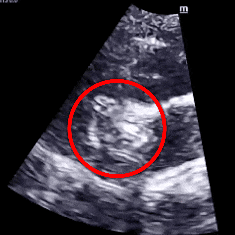

经食道心脏超声:四腔心切面缺口径宽约0.35cm,缺损边缘距二尖瓣环约2.1cm,距房顶约2.5cm,大动脉短轴切面缺口经宽0.36cm,主动脉后方无残边。双房切面缺口径约0.35cm,缺损边缘距上腔静脉约2.6cm,距下腔静脉约2.7cm。CDFI:房间隔连续中断处见左向右分流信号。

TEE可见房间隔中断出左向右分流

TEE测量缺损大小

肺动静脉CTA未见异常;经食道超声检查明确为小房缺,缺损直径约0.35cm。